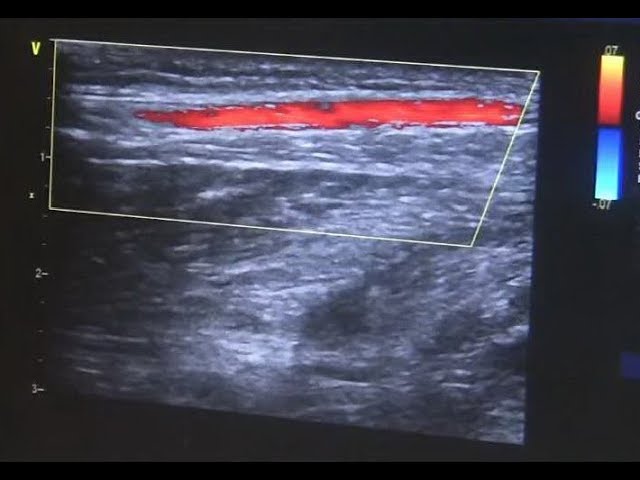

Помимо визуализации анатомического строения, важной задачей УЗИ сосудов верхних конечностей является оценка характера и вида кровотока. В таких случаях, помимо стандартного вида обследования, применяется ультразвуковая допплерография сосудов (УЗДГ). Методика основана на эффекте Допплера (изменение частоты при отражении от движущихся элементов).

Также важным аспектом диагностики является определение параметров самого сосуда. Для этого используется дуплексное сканирование. В результате обследования можно получить достоверную информацию о величине просвета, извитости русла, толщине стенок, наличии пристеночных образований (тромбов, атеросклеротических бляшек).

В данном видеообзоре УЗ-специалист расскажет и покажет как проводится исследование:

Во время УЗИ артерий и вен верхних конечностей важно оценить состояние стенок сосуда, его просвет, наличие пристеночных тромбов или другие патологии. Также необходимо исследовать параметры кровотока: его скорость, наличие турбулентности, давление.

В норме стенка артерии или вены структурирована, имеет одинаковую ширину на всем протяжении. Просвет должен быть свободен. Кровоток имеет линейный характер, постоянную скорость. Давление в разных отделах сосудистой системы может меняться.